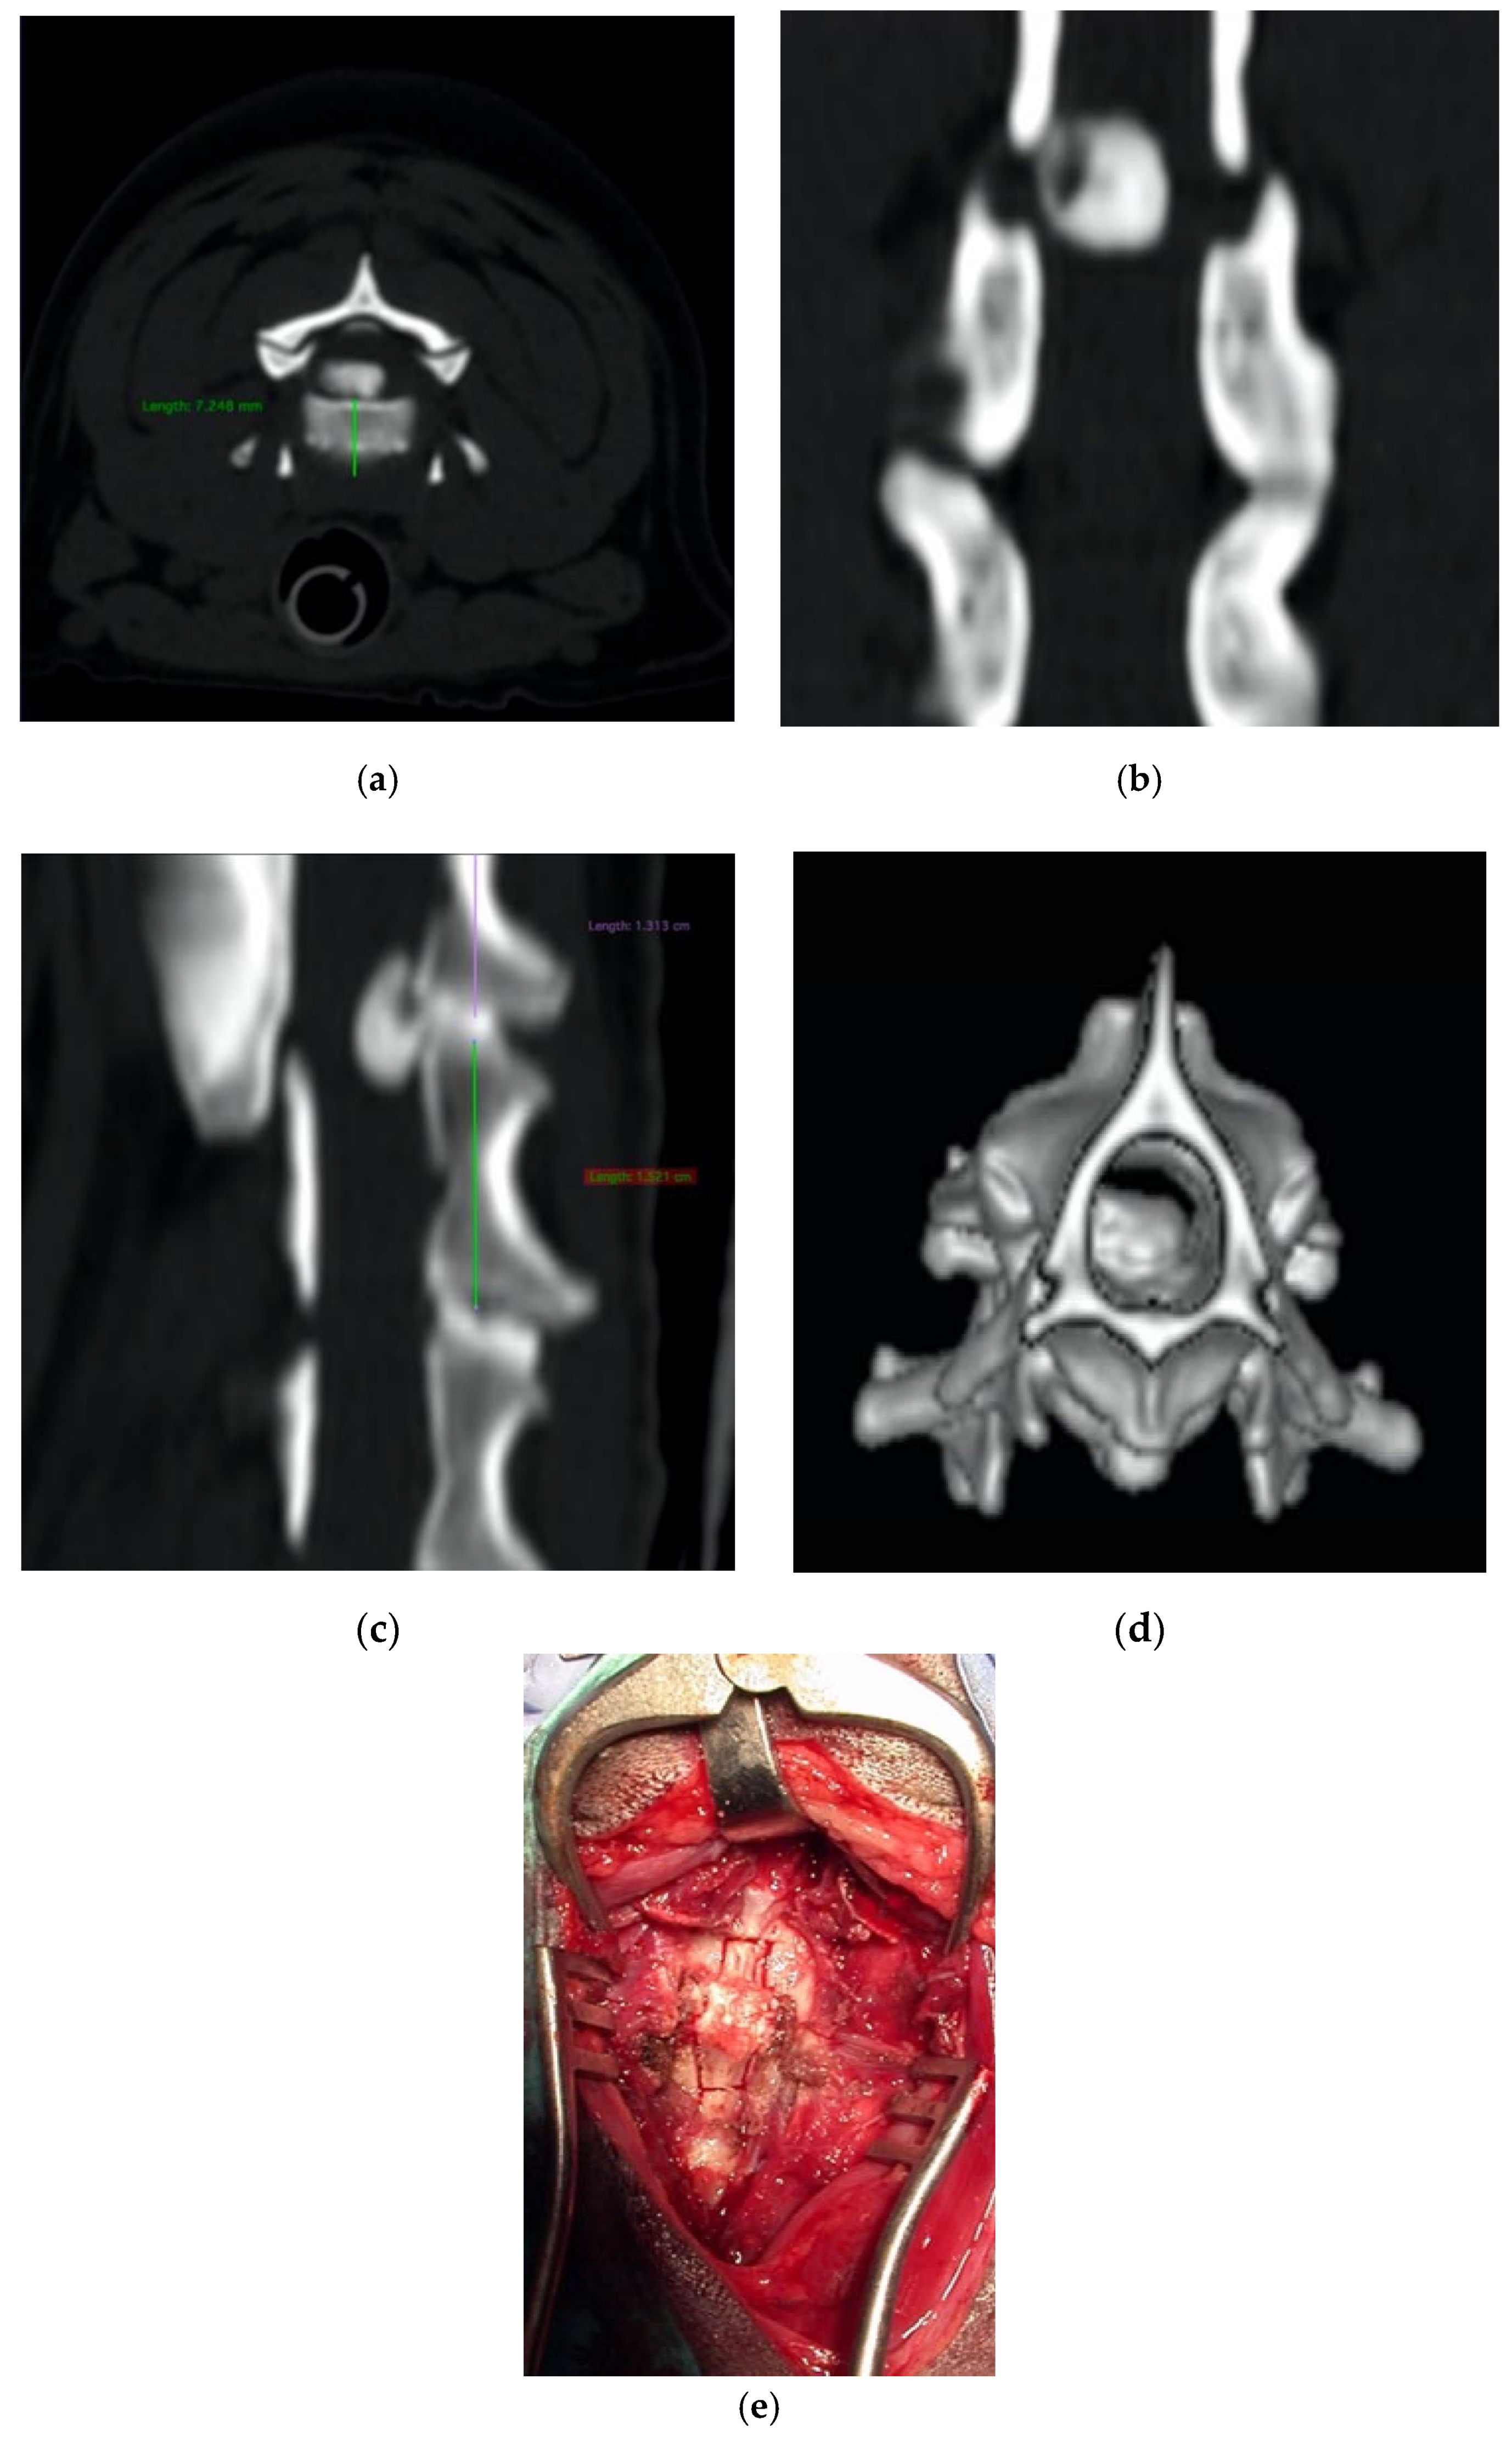

Dachshund, female, seven years old, 8 kg, suffering from a progressive tetraplegia due to a cervical disk extrusion involving the C2-C3 space.

The dog underwent a ventral slot decompression by means of the piezoelectric bone scalpel with a curved long insert, which resulted in being very helpful, considering the depth of the surgical field compared to the dorsal approach (Figure 7). Two week later, the motor deficits significantly improved, and no signs of instability were documented.

Figure 7.

Axial (a), coronal (b), sagittal (c), and 3D (d) cervical CT scan showing a C2-C3 disk extrusion in a seven-year-old dachshund suffering from a progressive tetraplegia. Ventral slot decompression was obtained by means of long angled large saw tip (OT7, Osteotomy Tips Kit, Mectron Medical Technology, Genoa, Italy) (e).